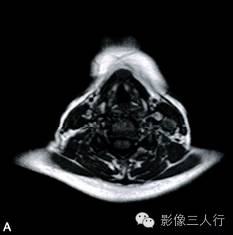

A~B. T1WI横断位;C~D. T2WI压脂横断位; E~F. T1WI压脂增强横断位;G. HE×100

卵圆形结节影位于舌骨中线,T1WI呈低信号,T2WI压脂序列呈稍高信号,信号均匀。增强后明显均匀强化,约1.3cm×0.8cm×1.6cm,其右前方下颌间隙内亦见一小结节,约0.7cm×0.4cm×0.5cm,信号特点与舌骨中线结节大致相同。颈部软组织结构清楚,未见异常信号影,气管居中,无受压或移位。颈部MRI平扫两侧见正常甲状腺组织,信号欠均匀(图A~F)。